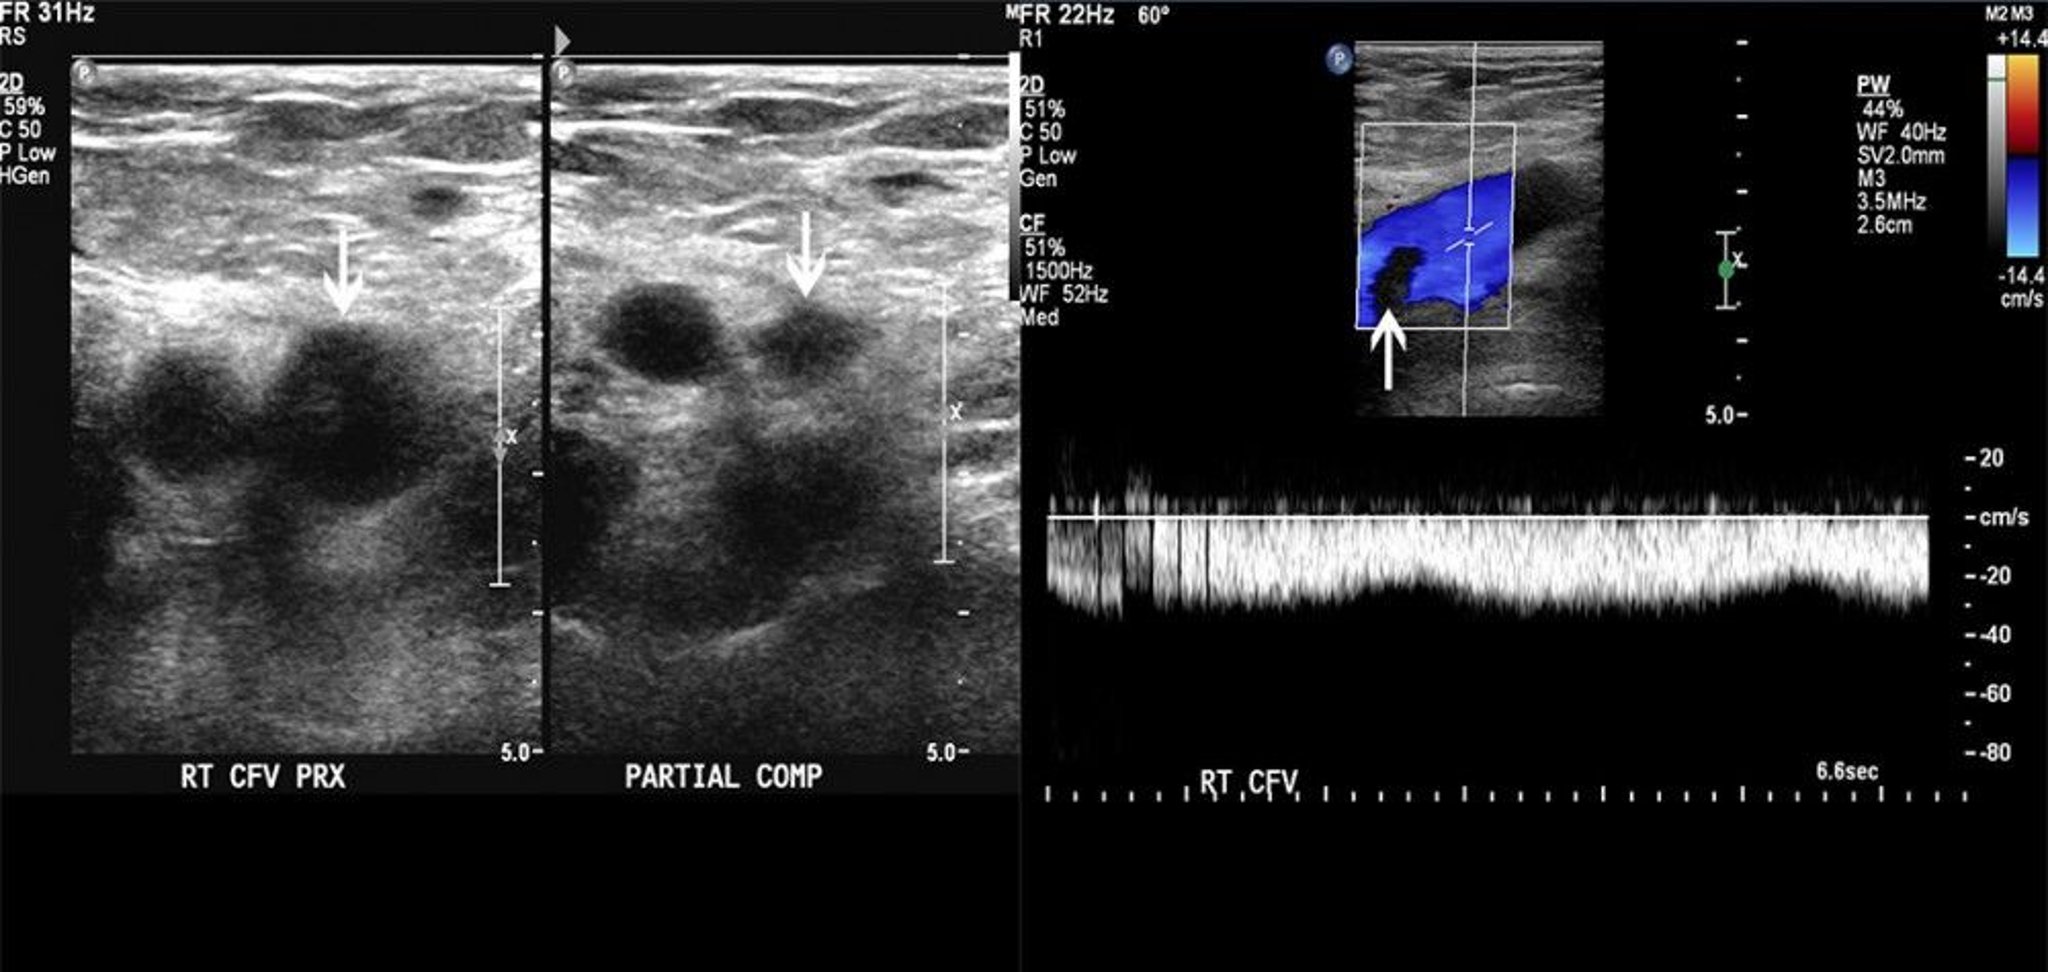

Doppler Ultrasound of a Patient with a Thrombus in Femoral Vein

The image on the left shows partial compressibility of the common femoral vein (arrows). The image on the right shows a filling defect on color Doppler flow. These findings are consistent with thrombus.